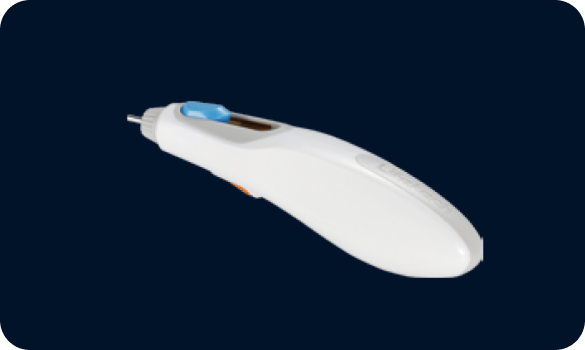

Lock/release mechanism, easy and convenient operation(1)

Soft delivery cable, minimizing the unwanted damage of heart or vessel tissue